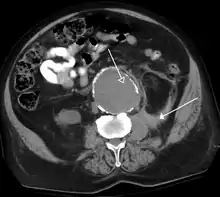

FIGURE 1. Non-contrast CT demonstrating multiple bilateral renal calculi (arrows), which can be obscured on contrast-enhanced images, particularly delayed images when there is excreted contrast in the renal collecting system; axial left, coronal reformat on right.

Non-contrast CT scans Figure 1a (left) and 1b (right) are of limited use for the differentiation of soft tissue structures. However, materials like blood, calcium (renal stones, vascular atherosclerosis), bone, and pulmonary parenchyma are highly visible and can usually be adequately assessed with non-contrast CT. For example, in the abdomen and pelvis, there are several indications for non-contrast imaging. These include: evaluation of renal calculi; assessment for gross intra-abdominal hemorrhage; and post-endostent volume measurements. In addition, non-contrast images are often obtained in conjunction with contrast enhanced images in evaluating potential renal transplant donors and in the evaluation of the pancreas (in combination with contrast phases). Of note, dual-energy CT and the development of virtual “non-contrast” images may ultimately obviate the combination scans. Additionally, CT angiography examinations performed for pathologies like aneurysms and dissection are frequently performed in conjunction with non-contrast imaging. The non-contrast images facilitate the differentiation of active extravasation or acute bleeding from vascular calcifications.